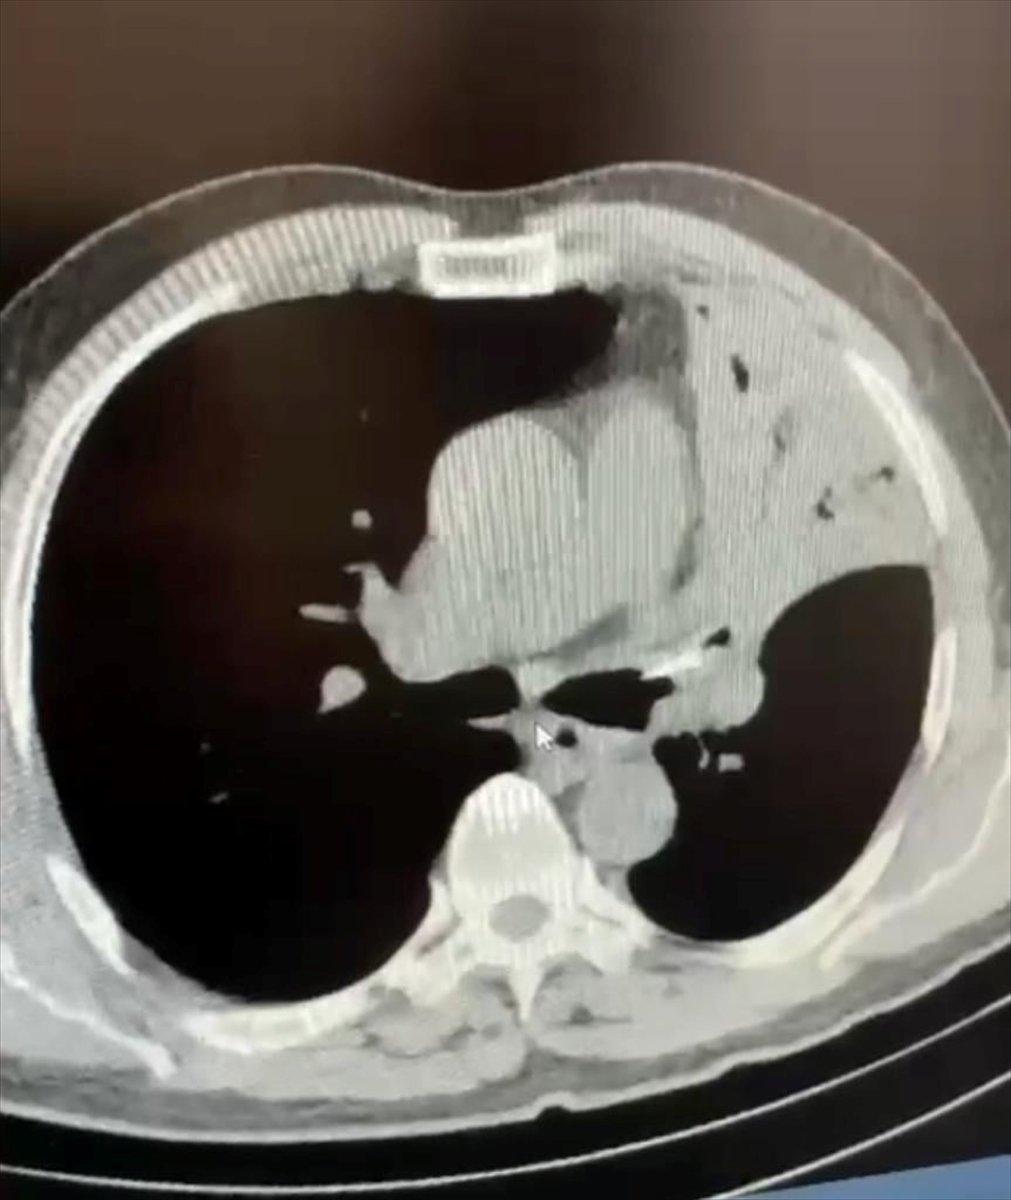

Bolu’da 5 yıl boyunca öksürük, şiddetli ağrı ve sırtında yanma şikayeti ile hastaneye başvuran hastanın akciğerine, yediği tavuğun lades kemiğinin sağlandığı tespit edildi.

AA’nın haberine göre; 5 yıl boyunca sol akciğerinde lades kemiğiyle yaşamını sürdüren hastanın şifa bulduğu.